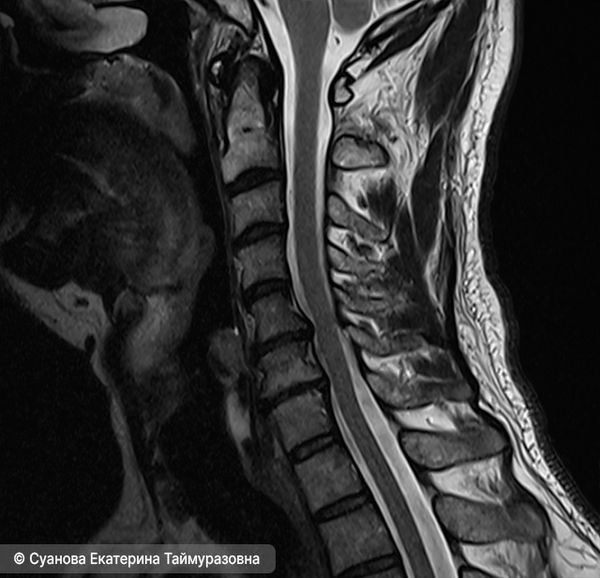

Выпрямление шейного лордоза с грыжей и протрузиями

- Магнитно-резонансная томография (МРТ) — с её помощью можно увидеть изменения мягких тканей, хрящей, костей, связок и сосудов, в том числе грыжевые выпячивания (экструзии) дисков и их контакт с нервными структурами. Она также показывает воспалительные процессы, опухолевые и сосудистые новообразования.